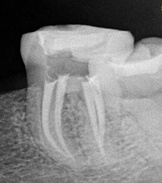

Es un procedimiento que

tiene como finalidad evitar la perdida del diente.

Para ello, se extrae la pulpa dental, se desinfecta y posteriormente se rellena y sella con material inerte y biocompatible.

¿Qué es una endodoncia?